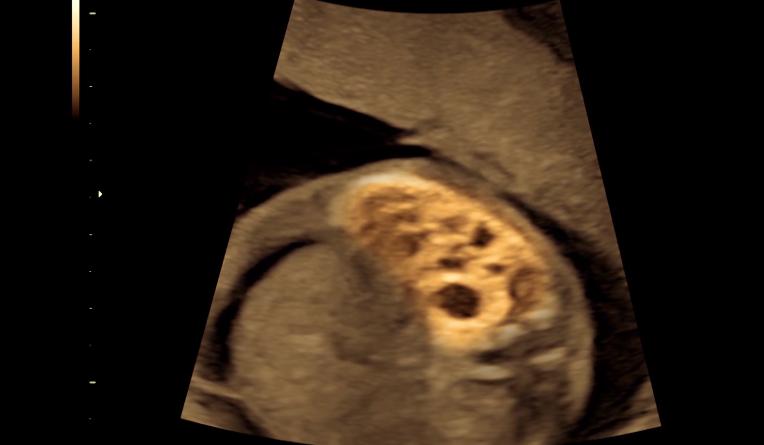

在B超的投影仪上,胎儿的大腿骨和髋骨的连接角度几乎接*平近**角,但正常情况下,胎儿的两根骨头的角度应该呈直角。

从检查结果可以看到,胎儿的大腿骨比正常的长度要短,其次大腿骨顶部不是呈直角,这也就意味着,他们夫妻辛苦孕育的下一代也是侏儒人。